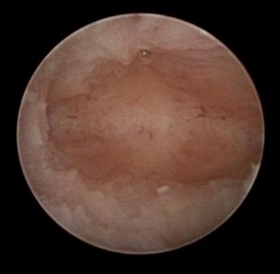

当院では子宮鏡検査で、子宮内膜ポリープ、小さな子宮粘膜下筋腫、子宮内癒着、慢性子宮内膜炎によるマイクロポリープを認めた患者様に対する子宮鏡手術として、Hologic社の『MyoSure』を用いて、年間500例以上の子宮鏡手術を行っております。

一般的な子宮内膜ポリープの摘出方法は、ループ状の電気メスや鉗子を用いて切除するため、子宮内膜の熱損傷や、正常な内膜まで損傷してしまうリスクがあります。

『MyoSure』は、細い子宮鏡で子宮内を確認しながら、病変を少しずつ切断して摘出するため、子宮内膜へのダメージがありません。